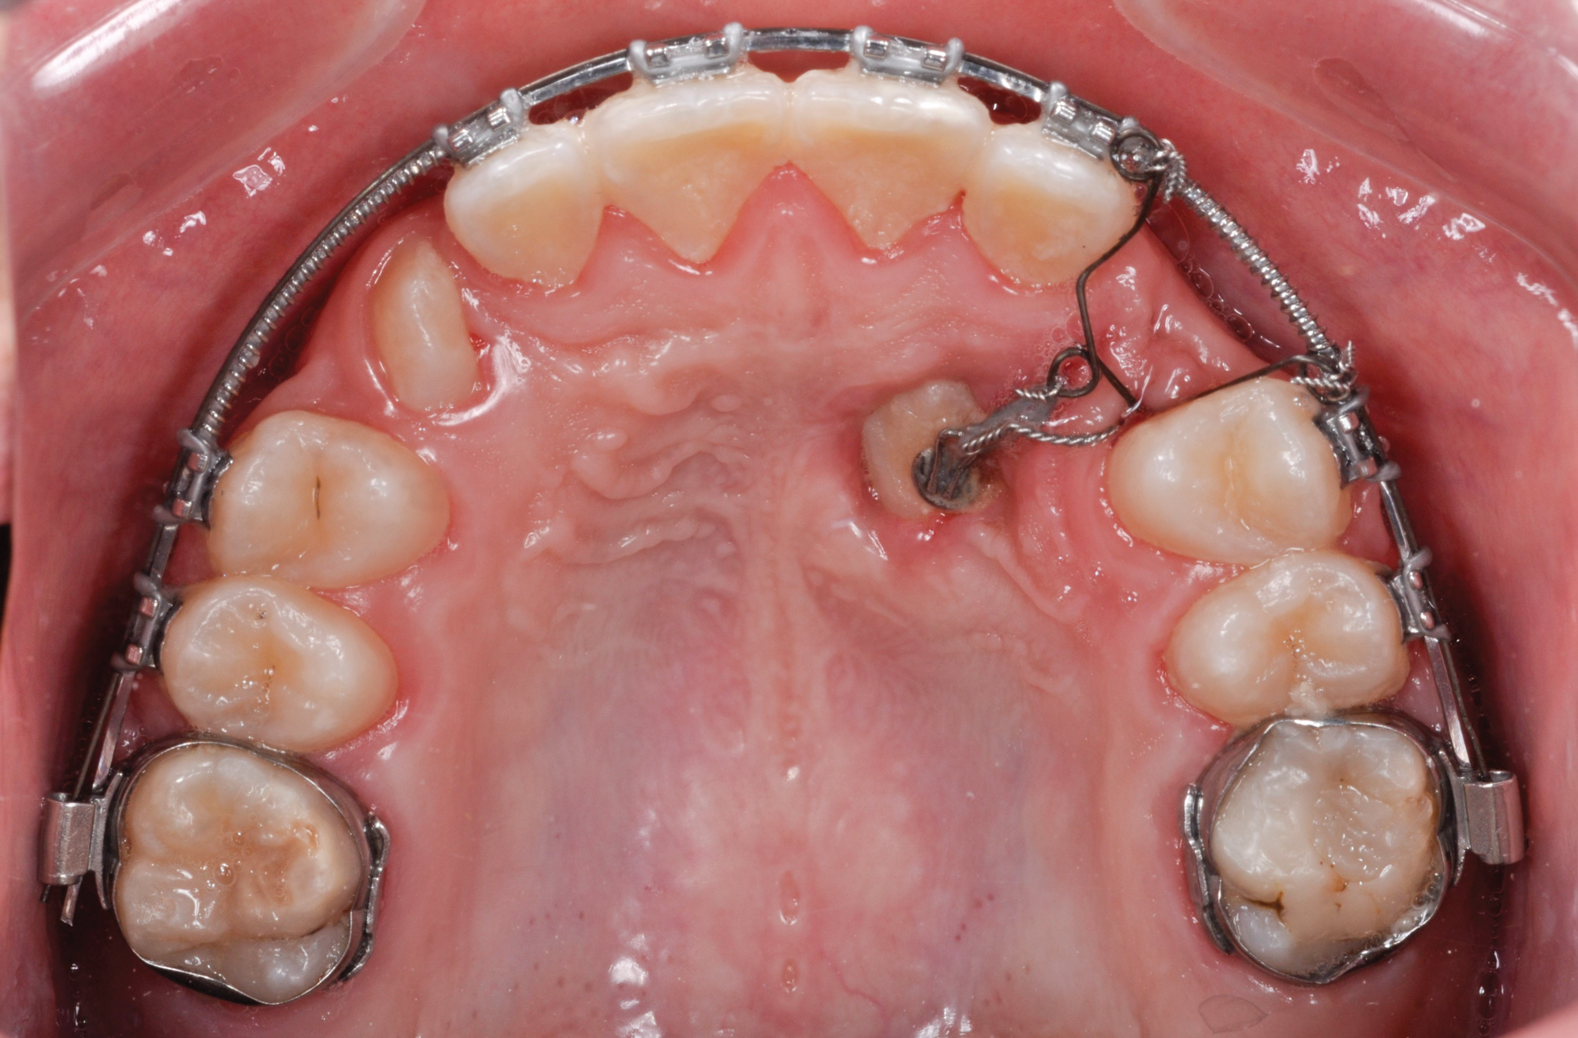

Fig 8. Open exposure (Fig 8) with spontaneous eruption for 7 months. Once the canines reached the occlusal plane, buccal traction was performed for an additional 5 months. Total treatment time to move the bilateral palatal impacted canines into the arch was 12 months (Fig 9).

Figure 8

Fig 9. Open exposure (Fig 8) with spontaneous eruption for 7 months. Once the canines reached the occlusal plane, buccal traction was performed for an additional 5 months. Total treatment time to move the bilateral palatal impacted canines into the arch was 12 months (Fig 9).

Figure 9